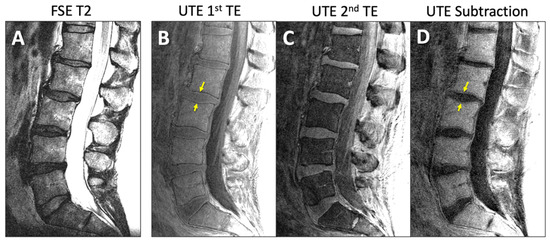

- Bae, W.C.; Statum, S.; Zhang, Z.; Yamaguchi, T.; Wolfson, T.; Gamst, A.C.; Du, J.; Bydder, G.M.; Masuda, K.; Chung, C.B. Morphology of the Cartilaginous Endplates in Human Intervertebral Disks with Ultrashort Echo Time MR Imaging. Radiology 2013, 266, 564–574. [Google Scholar] [CrossRef]

- Finkenstaedt, T.; Siriwananrangsun, P.; Masuda, K.; Bydder, G.M.; Chen, K.C.; Bae, W.C. Ultrashort time-to-echo MR morphology of cartilaginous endplate correlates with disc degeneration in the lumbar spine. Eur. Spine J. 2023, 32, 2358–2367. [Google Scholar] [CrossRef]

- Law, T.; Anthony, M.P.; Chan, Q.; Samartzis, D.; Kim, M.; Cheung, K.M.; Khong, P.L. Ultrashort time-to-echo MRI of the cartilaginous endplate: Technique and association with intervertebral disc degeneration. J. Med. Imaging Radiat. Oncol. 2013, 57, 427–434. [Google Scholar] [CrossRef] [PubMed]